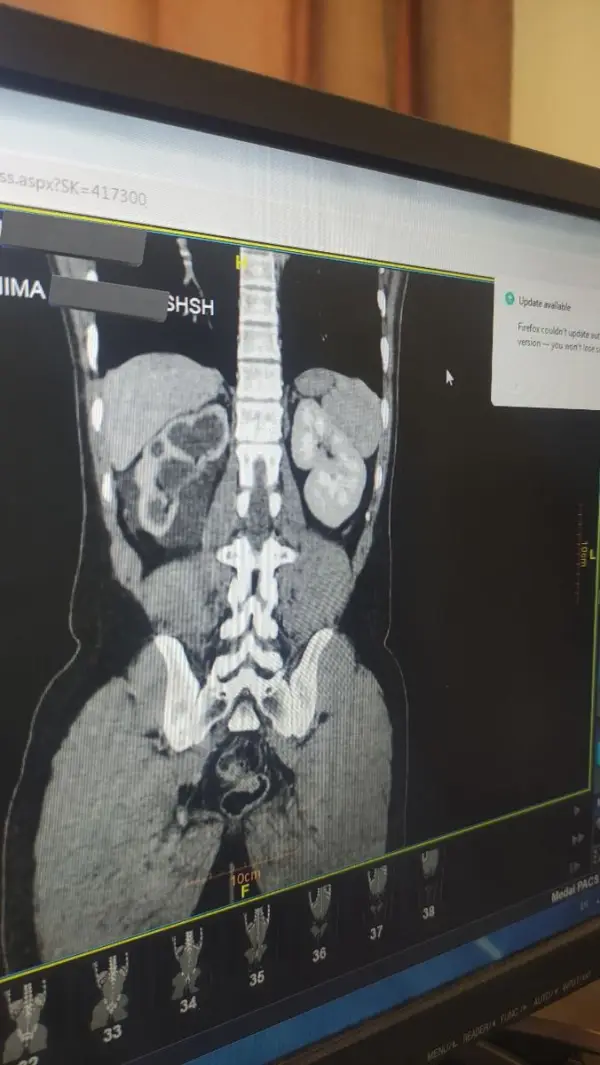

بیمار بخت برگشته، پسر ۲۴ ساله دوستاش حین شوخی، با لگد زدن توی پهلوی راستش !!!

با درد شدید اومد اورژانس علائم حیاتی خوب بود

توی سیتی شکم لگن متوجه شدن که پارگی وسیع کلیه راست داشته!